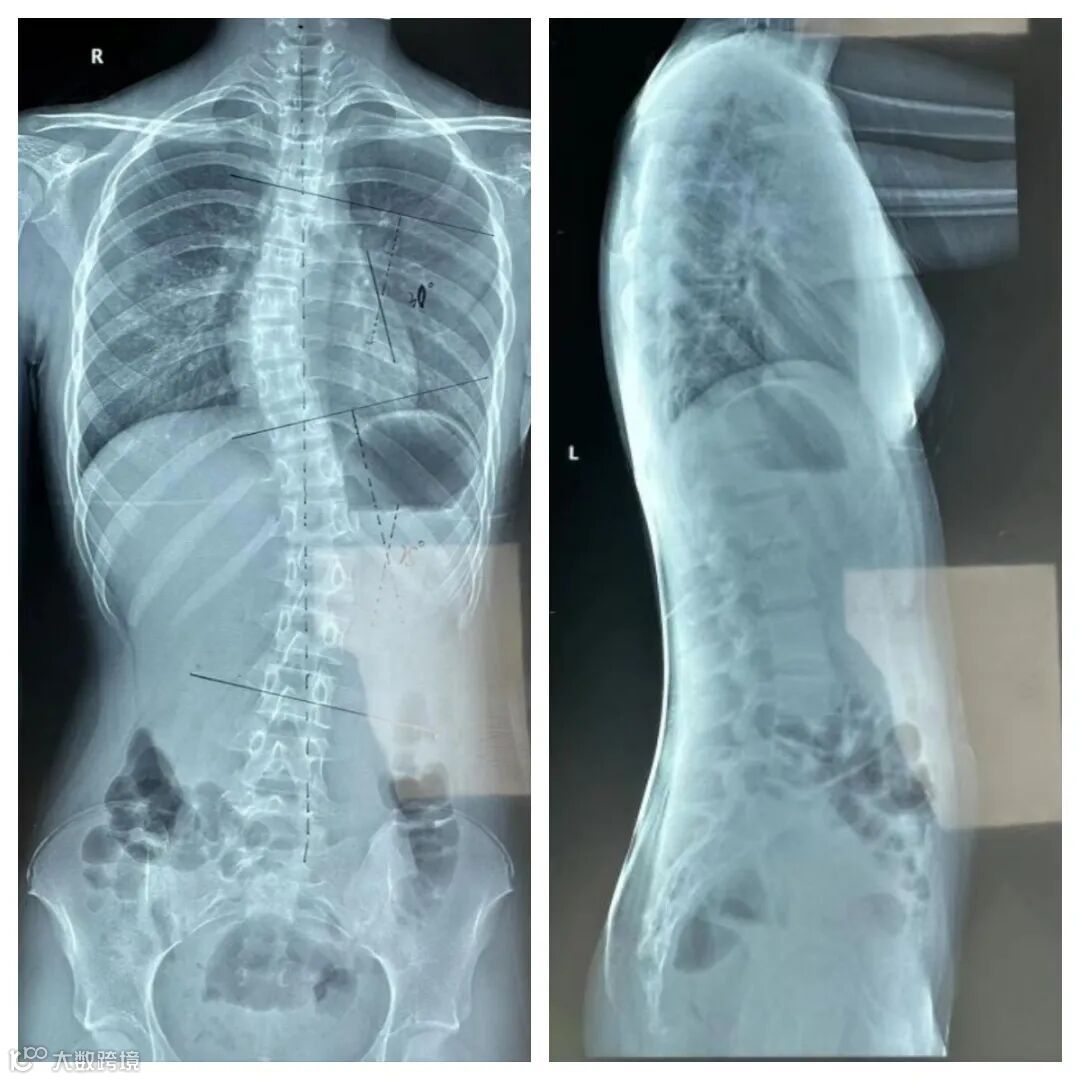

Y同学,女,12岁,初一,学习压力大,坐姿不好,偶然一次肺炎去拍片发现脊柱侧弯,因未达到手术指证,医生建议进行支具治疗。

穿戴前

1:首次制作支具前评估:胸段Cobb角30°,腰段Cobb角25°,椎体旋转度Ⅲ度,ATR=胸段8°,腰段7°,Risser症Ⅳ度,高低肩明显。

1:该患者虽然Risser症Ⅳ度,但坚持穿戴支具,保证支具穿戴松紧和每天穿戴时间,并有进行脊柱侧弯体操康复,相信后续矫正效果会很不错。

2:支具的作用相当于一个不会说话的老师,在没有康复老师监督和自己松懈的时候,对患者进行矫正和督促。